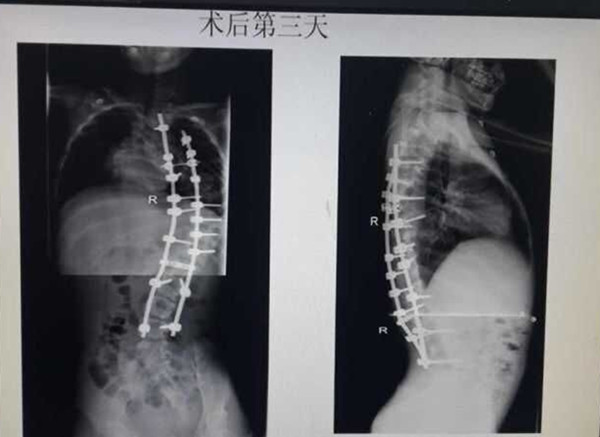

手术前,学科带头人贺西京教授、李浩鹏主任邀请有丰富麻醉经验的李有才教授,以及主管医生,根据患儿全身状况,进行细致的病例讨论,制定周密的手术方案。于8月18日,由贺西京、李浩鹏教授亲自主刀,主管医生张纯、杨宝辉、蔡璇等配合,李有才教授负责麻醉,对患儿实施全麻下全脊柱截骨矫形术,术中在严密保护脊髓的前提下,将脊椎一节节打断、截骨,再重新排列、固定。因脊柱畸形严重,常规固定方式无法完成,只能凭经验探索进行,多次进行术中透视。如此大范围脊柱矫形,风险极大,术中稍有不慎,无论是术中操作,还是骨片,都有可能损伤血管造成大出血,危及生命。在完成椎体截骨时,脊髓也要完成近120度的变位,此时极易损伤神经,风险极大。神经损伤会造成患儿终身瘫痪,双下肢丧失运动、感觉功能,并出现大小便失禁等,因此要求术者一定要心细,操作要轻、准。手术全程在诱发电位严密监测下进行,及时反复监测神经传导速度,判定神经功能。在手术、麻醉及护理人员的紧密配合下,经过近10小时紧张、细致的手术,手术取得成功,矫形由患儿颈后部到腰下段的脊柱全段,缝针36针,术中输血1800毫升,术中矫正脊柱畸形角度约120度。术后患儿即可平卧,背部大驼背畸形显著改善,双下肢感觉、运动良好,自解小便,目前正在积极康复中。